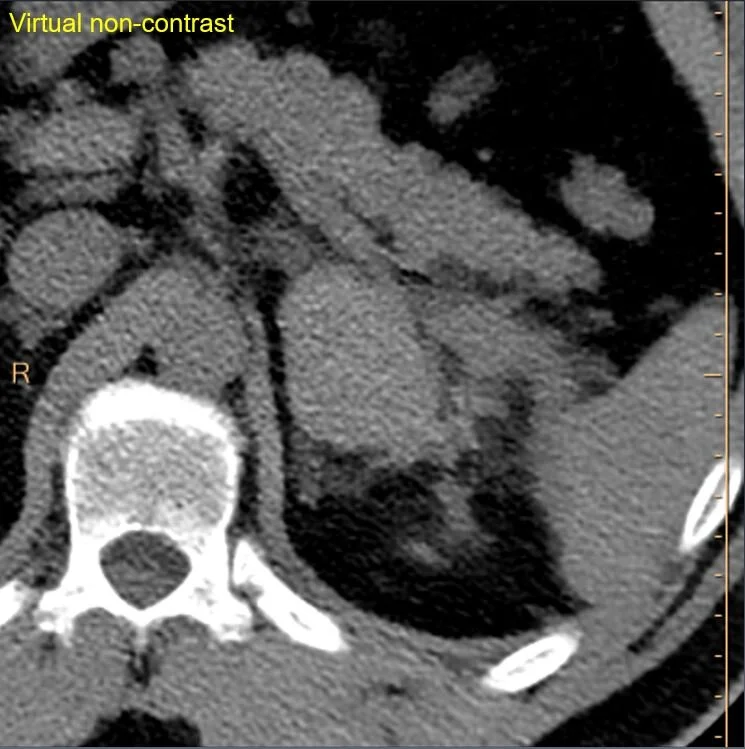

Spectral CT images show the “mass” is hyperdense on virtual non-contrast and has no iodine uptake. This is just a typical adrenal hematoma. On closer inspection, patient had a couple of rib fractures, but no other evidence of trauma.

VNC: Mass remains hyperdense